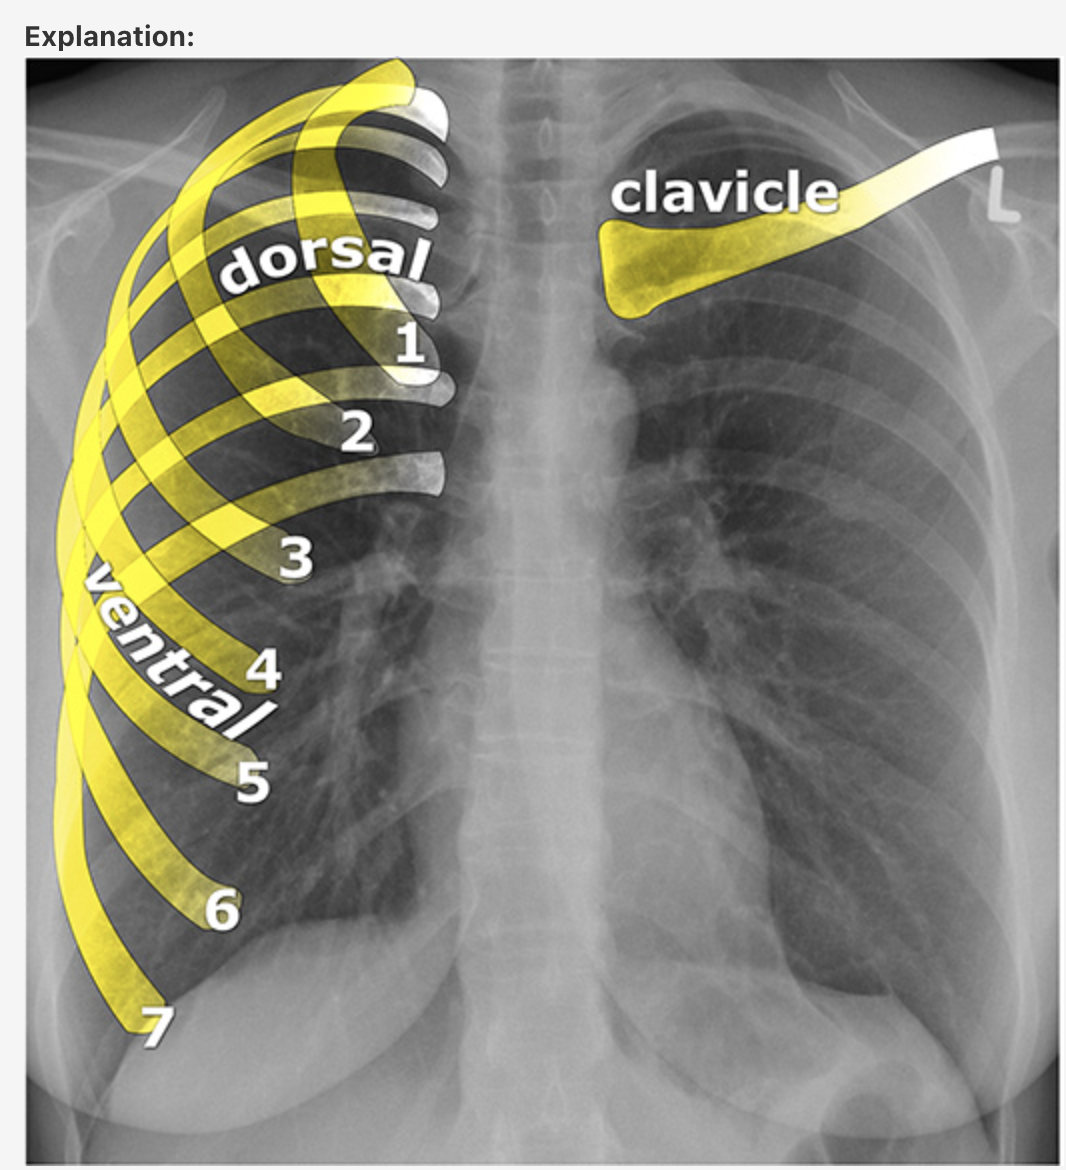

Answer: Chronic Obstructive Pulmonary Disease

In normal subjects, the diaphragm is intersected by the 5th to 7th anterior ribs in the mid-clavicular line - in this patient you can count up to 9 ribs before reaching the diaphragm - > hyperexpanded lungs.

Flattening of the diaphragm is also observed in this x-ray which is a reliable feature of lung hyperexpansion.